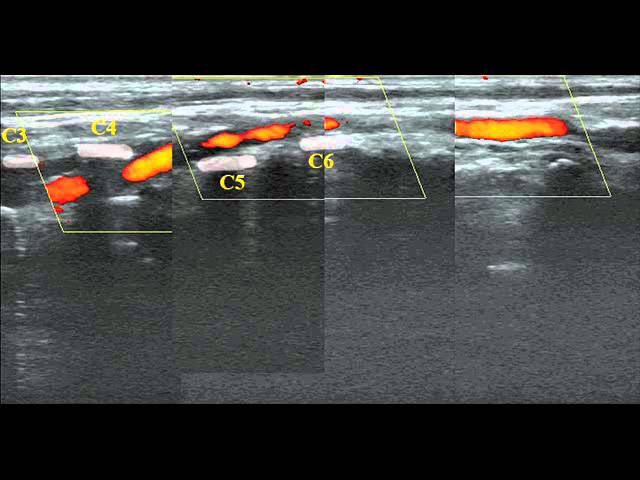

Чаще всего врачи в таких случаях назначают МРТ (магнитно-резонансную томографию), а при выраженных симптомах назначается ангиография или УЗИ позвоночных артерий.

При помощи указанных процедур можно точно определить состояние сосудов головного мозга, и если просвет канала сосуда сужен до 2 мм (нормой считается расстояние в 3,6-3,8 мм), то можно уже с уверенностью диагностировать гипоплазию и назначить лечение.